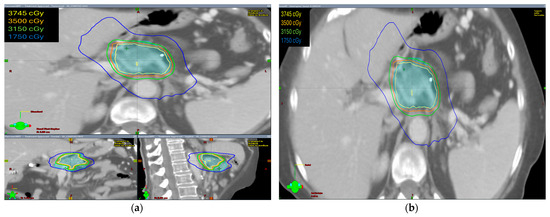

The radiation prescription dose was 35 Gy in five fractions in ten patients (58.8%). In five patients, the dose prescription was reduced to 30–33 Gy in five fractions and two patients received 40–50 Gy in five fractions. Median GTV volume was 28.60 cc (range 4.9–145.8 cc), median ITV was 29.15 cc (range 5.0–149.7 cc), and median PTV was 75.1 cc (range 19.9–255.3 cc). The isodose distribution for both abdominal compression and breath-hold technique is shown in Figure 1 and Figure 2, respectively.

The isodose distribution curves for target coverage and normal tissue dosing were evaluated. We found that the ITV was generated only in patients with abdominal compression to encompass the internal organ motion during treatment. Hence, PTV volumes were larger in these patients as compared with patients treated with breath-hold in which no ITV was drawn and smaller PTV volumes were irradiated.

Figure 2. The isodose distribution using the breath-hold technique (a) axial, coronal, and sagittal views (b) axial view.